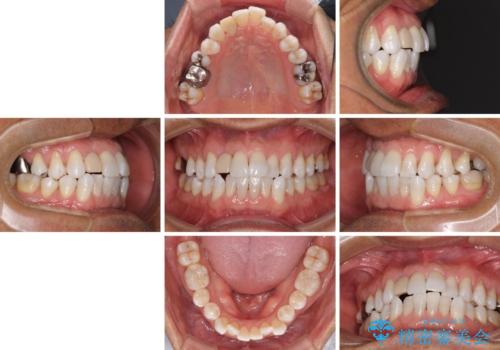

治療途中の前歯を治したい インビザライン矯正とオールセラミッククラウン

- 治療途中の前歯と上下前歯のデコボコ気にして来院された患者様です。

前歯のデコボコはインビザラインにより歯列を整え、その後に、前歯などをオーダーメイドタイプのオールセラミッククラウンにて補綴治療することとしました。

長時間のマウスピース装着に協力いただき、短期間で歯列をしっかりと改善することができました。

ホームホワイトニングを併用していただいたので、とても明るい口元に仕上がり、患者様には大変満足していただきました。